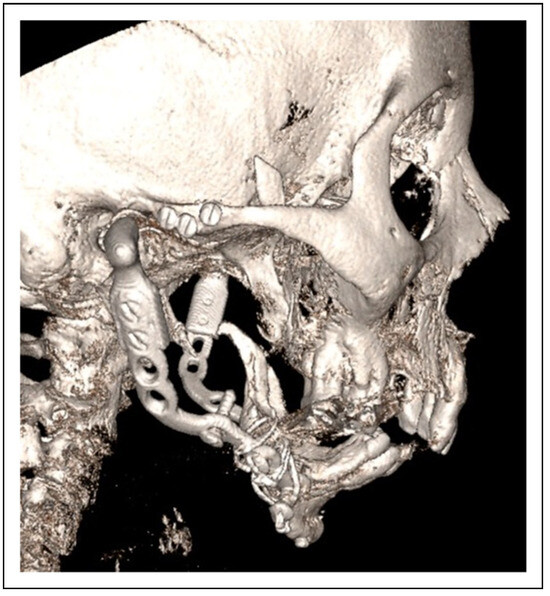

- Two-stage regime with simultaneous bone graft, patient 5

Two-Stage Regime, Patient 1